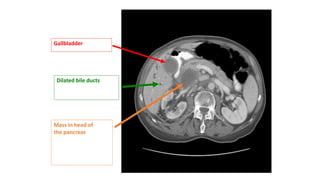

Radiological Investigation CECT Abdomen

• Higher Sensitivity and Specificity than USG for detection of bile

duct/pancreatic masses of 1-2 cm diameter.

• It is useful in determining resectability of cancer of Bile Duct or

Pancreatic Head Masses.

• It visualise the course of Bile Duct better than USG and hence more

likely demonstrated the level & Cause of Ductal Obstruction.

• Although USG better (more Sensitive )than CT Scan for detecting GB

Stone CECT is better(More Sensitive) for documenting CBD Stone.

CECT Abdomen

CECT

• Best for Pancreatic

Carcinoma(Highly sensitive for

lesion >1mm).

Gallbladder

Dilated bile ducts

Mass in head of

the pancreas